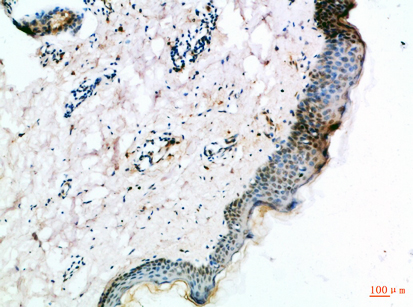

IHC (Immunohistochemisry)

(Immunohistochemical analysis of paraffin-embedded Human-skin, antibody was diluted at 1:100)